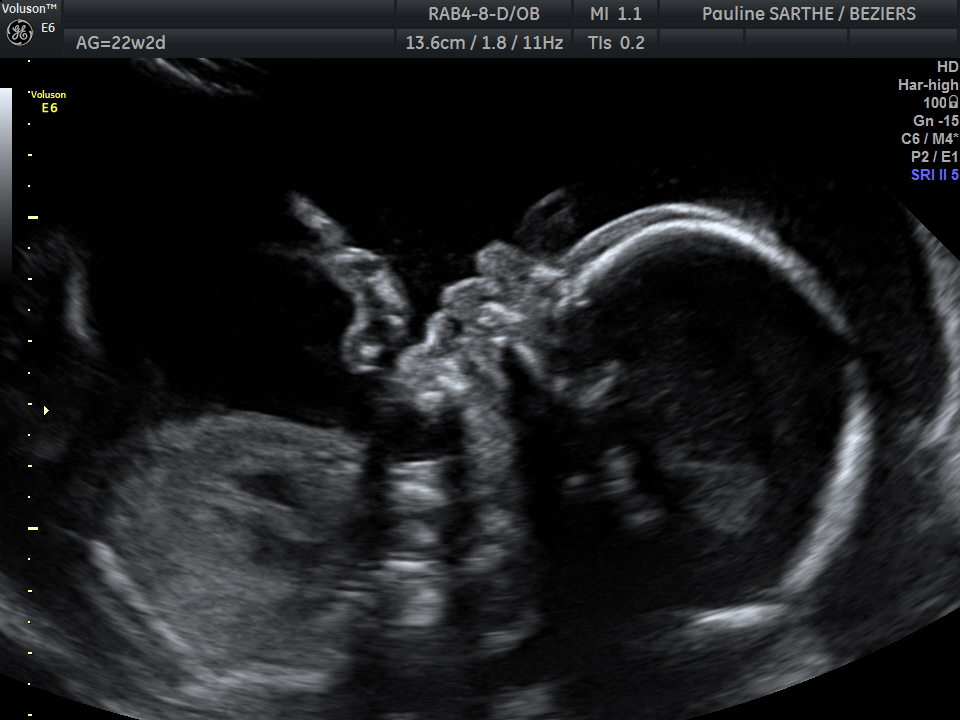

- l'échographie du 2 ème trimestre est réalisée entre 20 et 24 semaines d'aménorrhées (idéalement entre 21-23 semaines).Votre bébé a bien grandi et il est difficile de le visualiser en entier. C'est le moment idéal pour bien vérifier la vitalité de votre bébé à travers ses mouvements et le liquide amniotique , le bon développement de ses organes, sa croissance au travers des mesures de sa tête, de son périmètre abdominale et de son fémur qui permettront de donner une estimation de son poids ,et la localisation du placenta.

Parfois, si votre gynécologue ou votre sage-femme le demande , il peut être nécessaire d'effectuer une mesure du col. L’examen peut-être complété par des Dopplers analysant la bonne circulation du sang au niveau du cordon ombilical et des artères utérines.

Si la position du bébé le permet, une visualisation en 3D vous permettra d’avoir une première image de son visage.